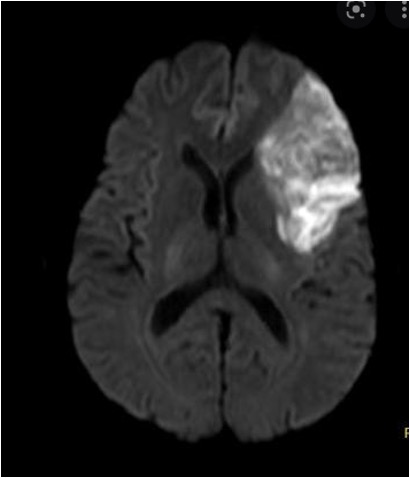

MRI with diffusion-weighted imaging is the most accurate for ischemic stroke usually within minutes of injury by detecting cytotoxic edema due to ischemia. It can miss an acute infarct in 7% of the patients: eg, posterior circulation, small brainstem strokes. Changes appear in the first few hours after stroke and is useful for unknown onset time (eg, >4.5h or wake-up strokes). The AHA approves tPA when DW-MRI is smaller than 1/3 of the MCA territory and no signal change on FLAIR. All stroke patients get an MRI within 24 hours.

T2 weighted sequences / Fluid attenuated inversion recovery (FLAIR) can diagnose sub-acute IS within 3-8h of symptoms, old strokes and SAH (but not as good as plain brain). Comparing the DWI with FLAIR is useful in determining if a wake-up stroke is a TNK candidate: +DWI but -FLAIR. FLAIR suppresses fluid on the images to make edema, old infarcts and glimpses more obvious. FLAIR lags DWI by hours.